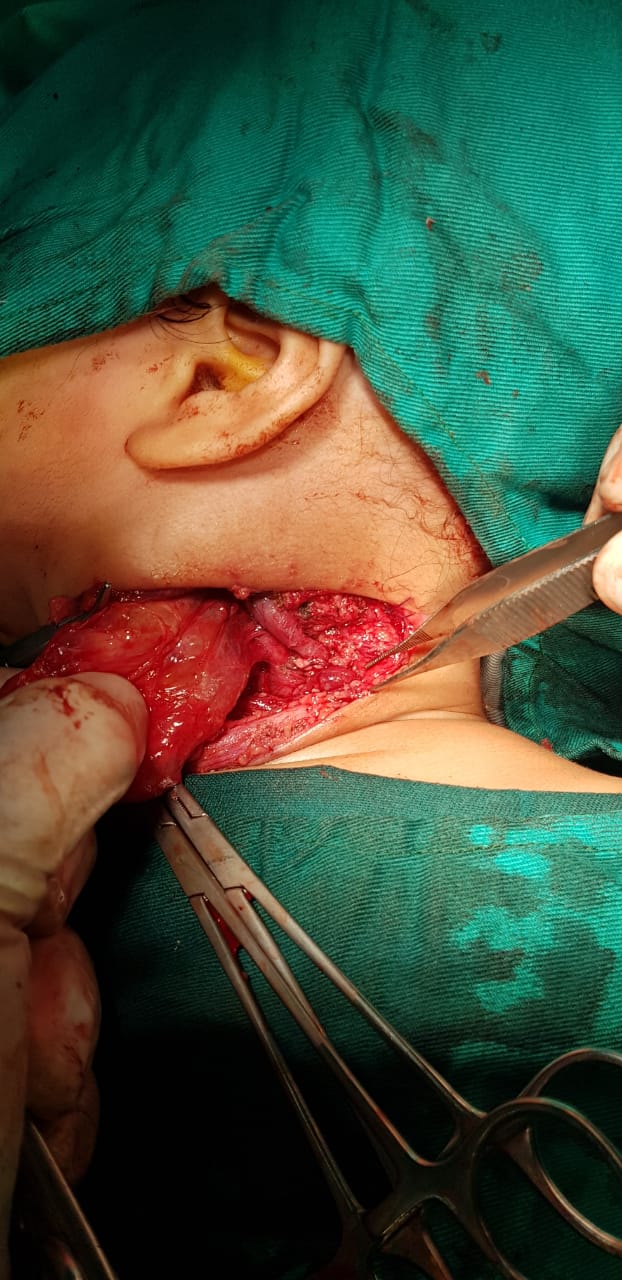

استئصال ورم من وجه طفل يزن 750 جراما بالإسكندرية

تمكن فريق طبي متميز بجامعة الإسكندرية، بقيادة الدكتور صابر وهيب، أستاذ جراحات الأطفال والتشوهات الخلقية، أستاذ بكلية الطب، من إزالة ورم يزن 750 جراما بوجه طفل عمره شهرين.

استئصال ورم يزن 750 جرام

قال الدكتور صابر وهيب، أستاذ جراحات الأطفال الخلقية بالإسكندرية، إنه تم استئصال الورم خلال عملية جراحية دقيقة استغرقت نحو ساعتين كاملتين.

وتابع: أورام الرقبة من الأورام الليمفاوية التي يتم ظهورها خلال الحمل أو بعد الولادة وأن العملية الجراحية التي أجريت لهذا المولود البالغ من العمر شهرين إذ تم استئصال الورم بالكامل وأنه كان يزن 750 جراما واستغرقت العملية نحو ساعتين وهذا تحدي أمام الجراحة الدقيقة التي يتم إجرائها.

صورة عملية جراحية لطفل